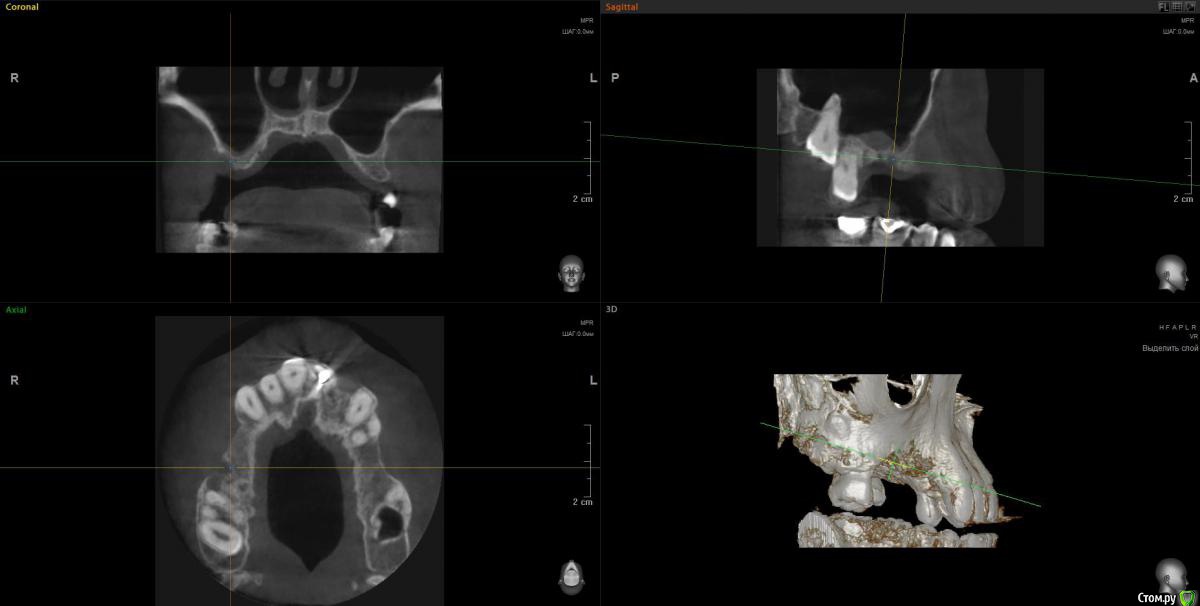

Просьба ко всем не равнодушным! Глянуть КТ верхней челюсти, 27 зуб  и место где удалили 16, может ещё где-то могут быть проблемы.  На фото видно где покраснение на дёснах, в этих местах возникают боли при движении головой. Бывает боль слева если засыпаю на левой стороне. Набуханий или флюсов нигде не видно.Прошу делиться мнениями, для меня это очень - очень важно. Стоматолог визуальных проблем на месте удалённого зуба не видит, всё зажило.

По данным КТ в зоне удалённого зуба 16 ничего особенного, разве что, ретенированный (непрорезавшийся) зуб 18.

Зуб 27 требует внимания, необходим очный осмотр.

Также стоит обратить внимание на зубы 21 и 24